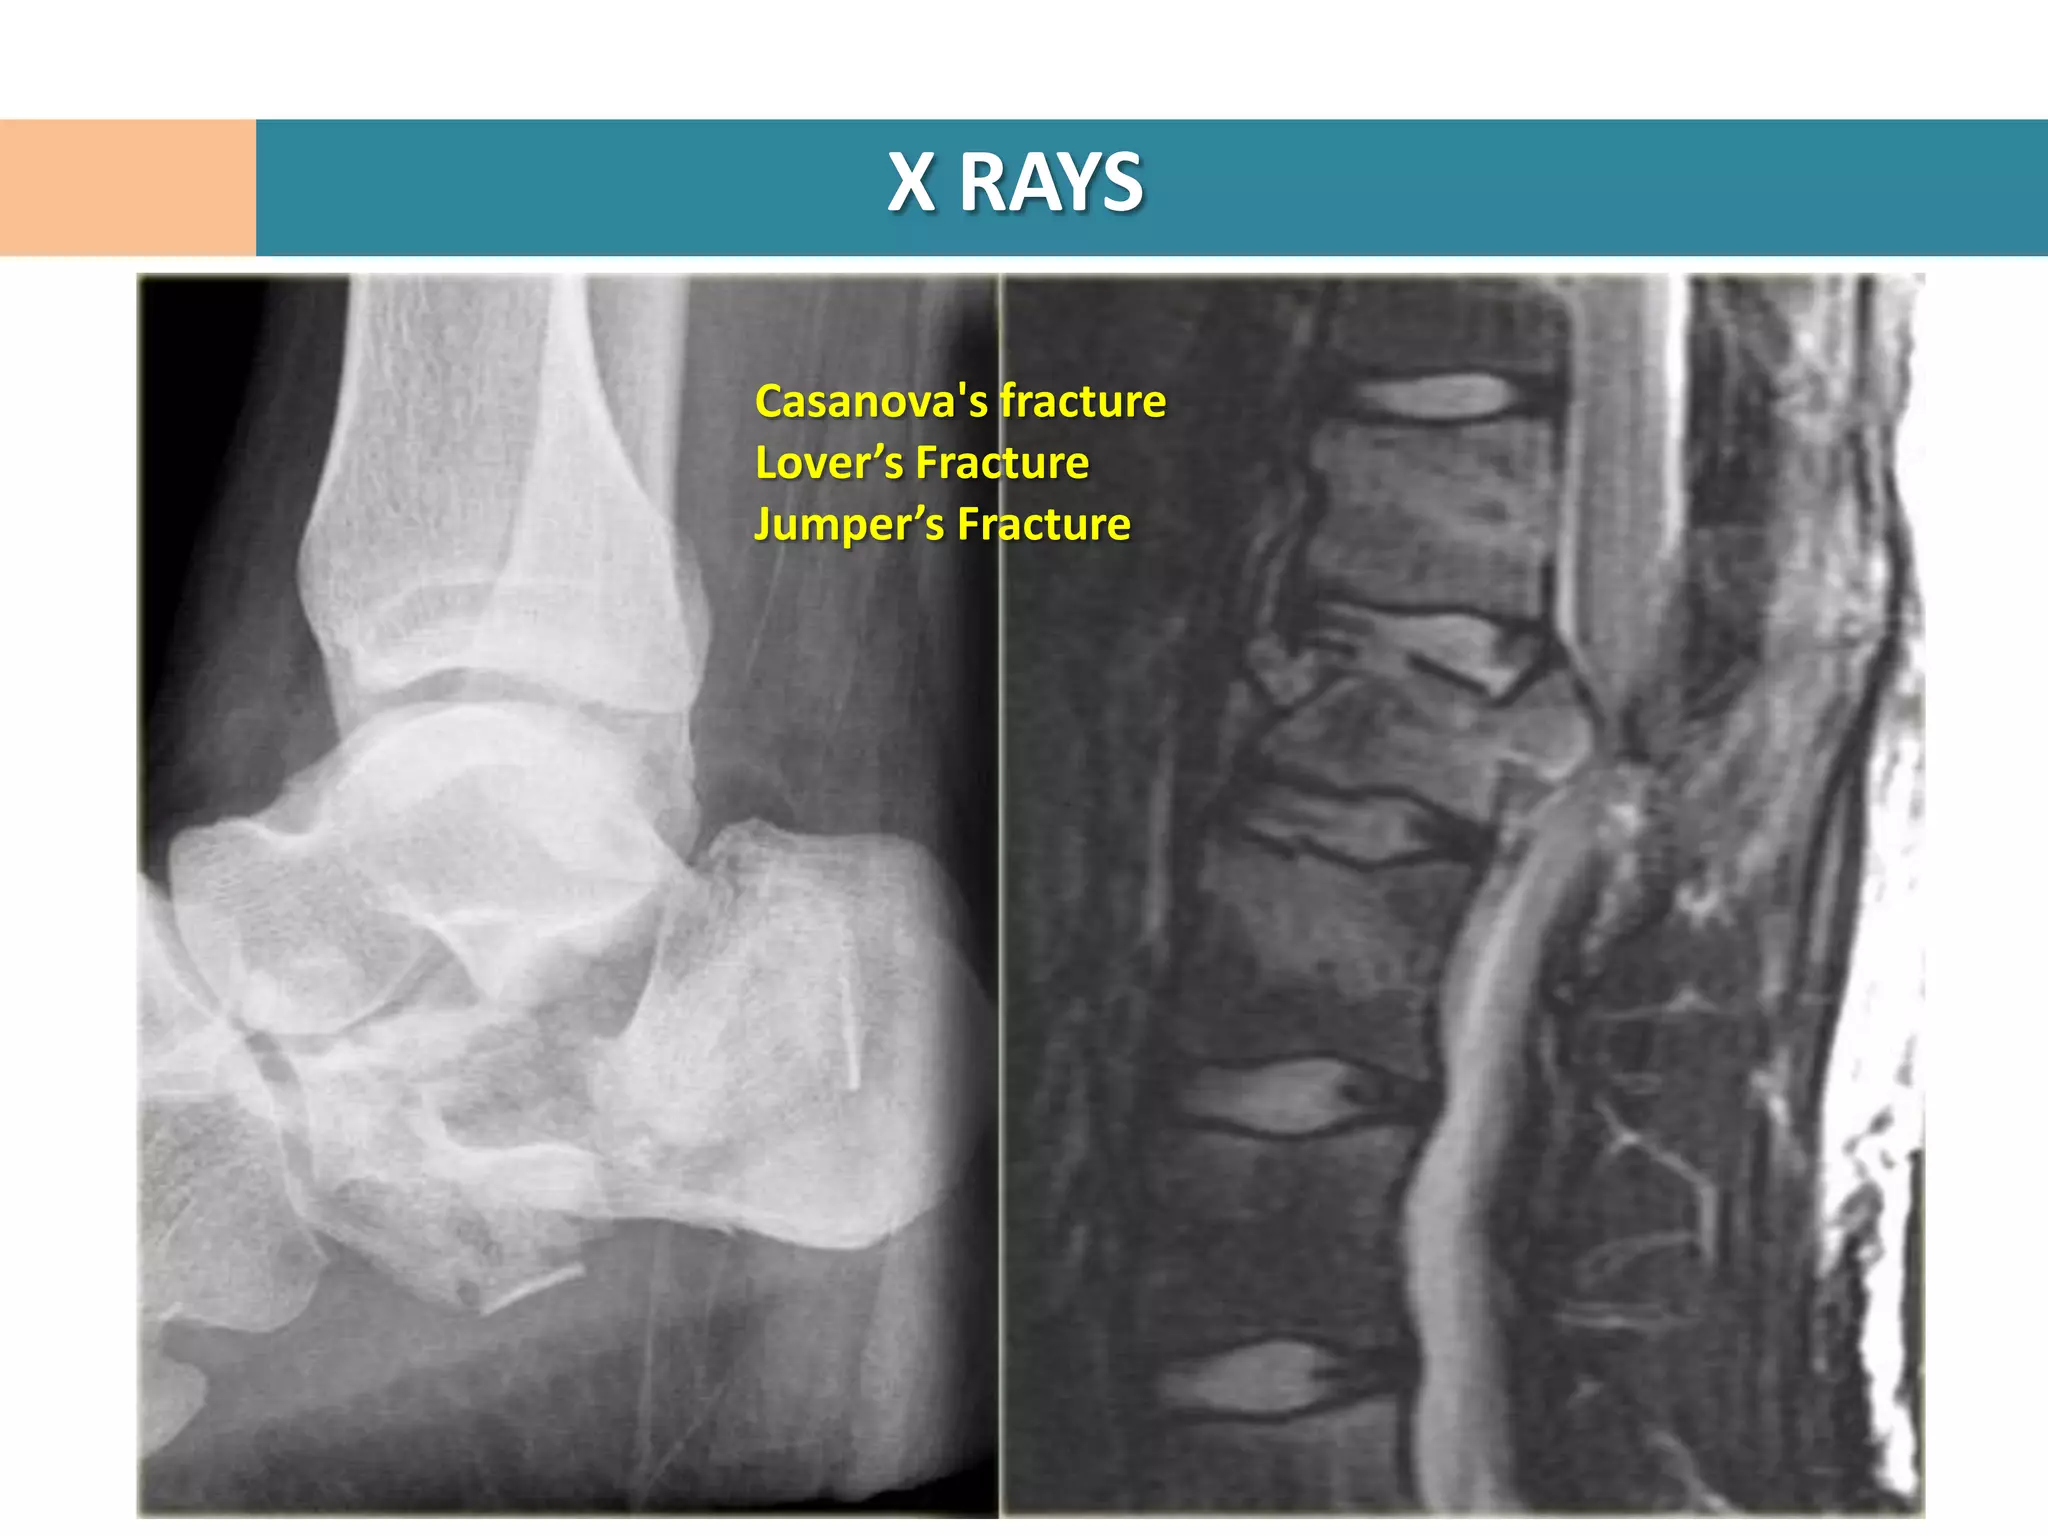

Lateral Hind foot

Confirms diagnosis of calcaneal #

Crucial angle of Gissane

Tuber angle of Boehler

Intraarticular #

Loss of ht of post facet

Reduced Boehler angle

Increased Gissane angle

Joint Depression vs Tongue type

Casanova's fracture

Lover’s Fracture

Jumper’s Fracture